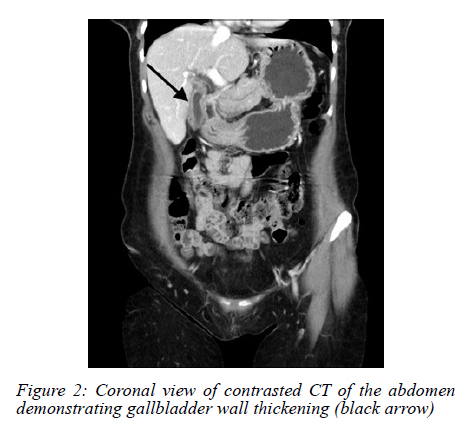

An abdominal ultrasound (AUS) showed a possible stone in the gallbladder neck, with a thickened and oedematous gallbladder wall (Figure 1). No masses were noted on sonar. The history of loss of weight was further investigated. A colonoscopy was performed, which was normal. A computed tomography (CT) scan did not show any concerning features, and a thickened gallbladder wall was once again visualised (Figure 2, 3).

Radiologically, CT and ultrasound findings are nonspecific, ranging from wall thickening to mass-like lesions with necrosis or calcification.68 These features overlap significantly with gallbladder malignancy or chronic inflammation,6,8 making preoperative diagnosis challenging. Radiologic "red flags" suggesting TB over carcinoma include gallbladder wall with necrotic core, multiple flecked calcifications, broad-based micronodular lesions, pericholecystic oedema, and necrotic lymph nodes.6 Consequently, in the absence of systemic TB features or pulmonary symptoms, most diagnoses hinge on postoperative histopathology, where necrotising granulomas with or without acid-fast bacilli confirm the diagnosis.9